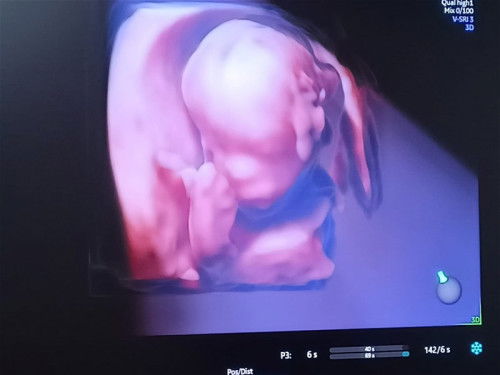

Bertanya dong Moms

Hai Moms, aku galau bgt nih , kmrin USG trs hasilny bgni , ini anak aku bbirny sumbing atau bukan ya? sangat OT akuuu ... kmrin ga nanya krna cm lihat skilas . pas plg rmh diliat2 lagi kok aneh ya .. mngkin mom2 dsni bs ad yg tahu ?😌 #21WeeksPregnant